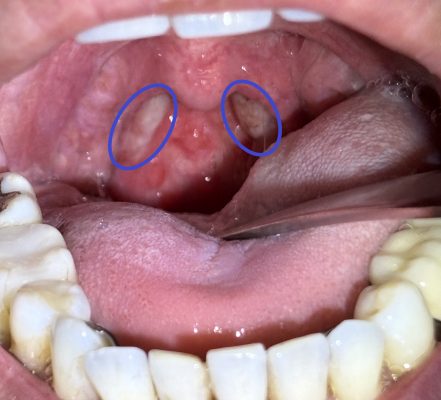

ノド👄を診てみます。

上記の 側索 と言われる部分に炎症を認めました(側索炎)。